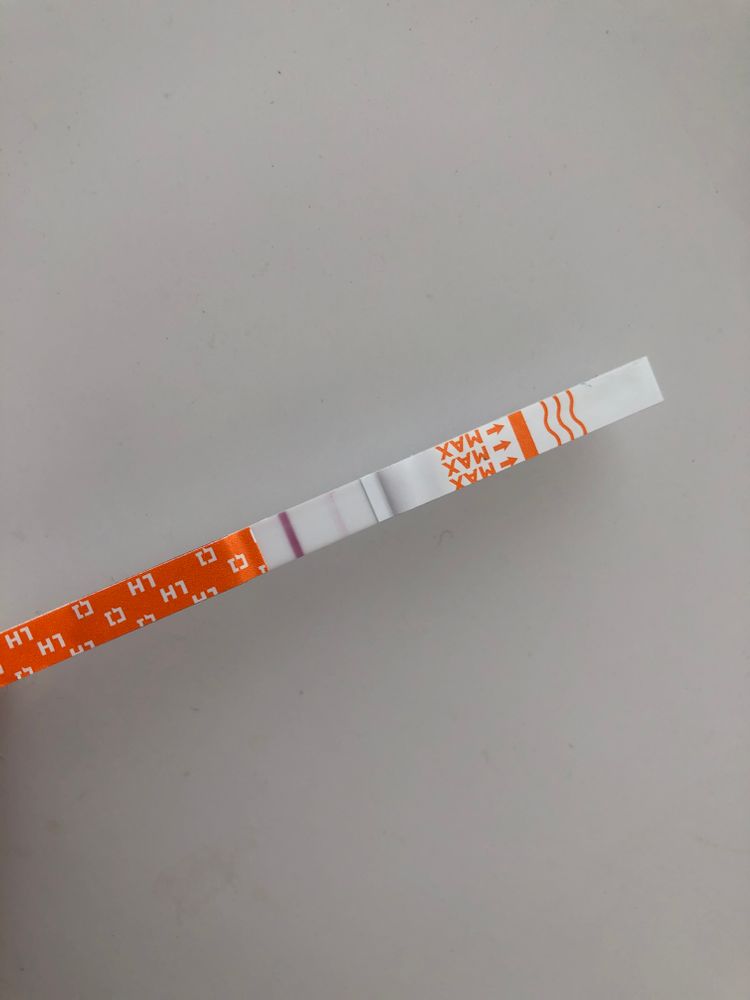

Полоска вроде не там где должна быть?

Полоска вроде не там где должна быть?

Я читала, что тесты на о показывают б. Возможно ли что и микроскоп на о, показал б.

Я уже ловила о в этом цикле, а по бт поймала из, ну как я думала, как тут вдруг. Вторая о или это первый признак б. Давайте попробуем разобраться. Подобного я р